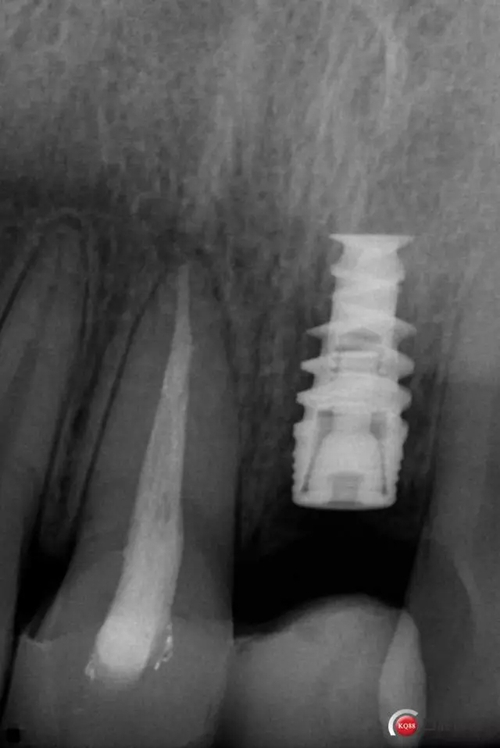

種植后修復(fù),我們要把握每一個(gè)細(xì)節(jié),比色,轉(zhuǎn)移桿的就位,我們必須把臨床做好,技工師傅才會(huì)給我們做出好的修復(fù)體,減少一些不必要的失誤,首先術(shù)前的檢查是必要一步 ,再是器械的準(zhǔn)備使我們臨床操作有條不紊,術(shù)前拍照,o-bite取咬合記錄,消毒修復(fù)術(shù)區(qū),旋出愈合基臺(tái),生理鹽水沖洗袖口,拍照袖口,安放合適轉(zhuǎn)移桿,拍X線見轉(zhuǎn)移桿就為良好,硅橡膠取模,術(shù)后旋回愈合基臺(tái),拍照比色。